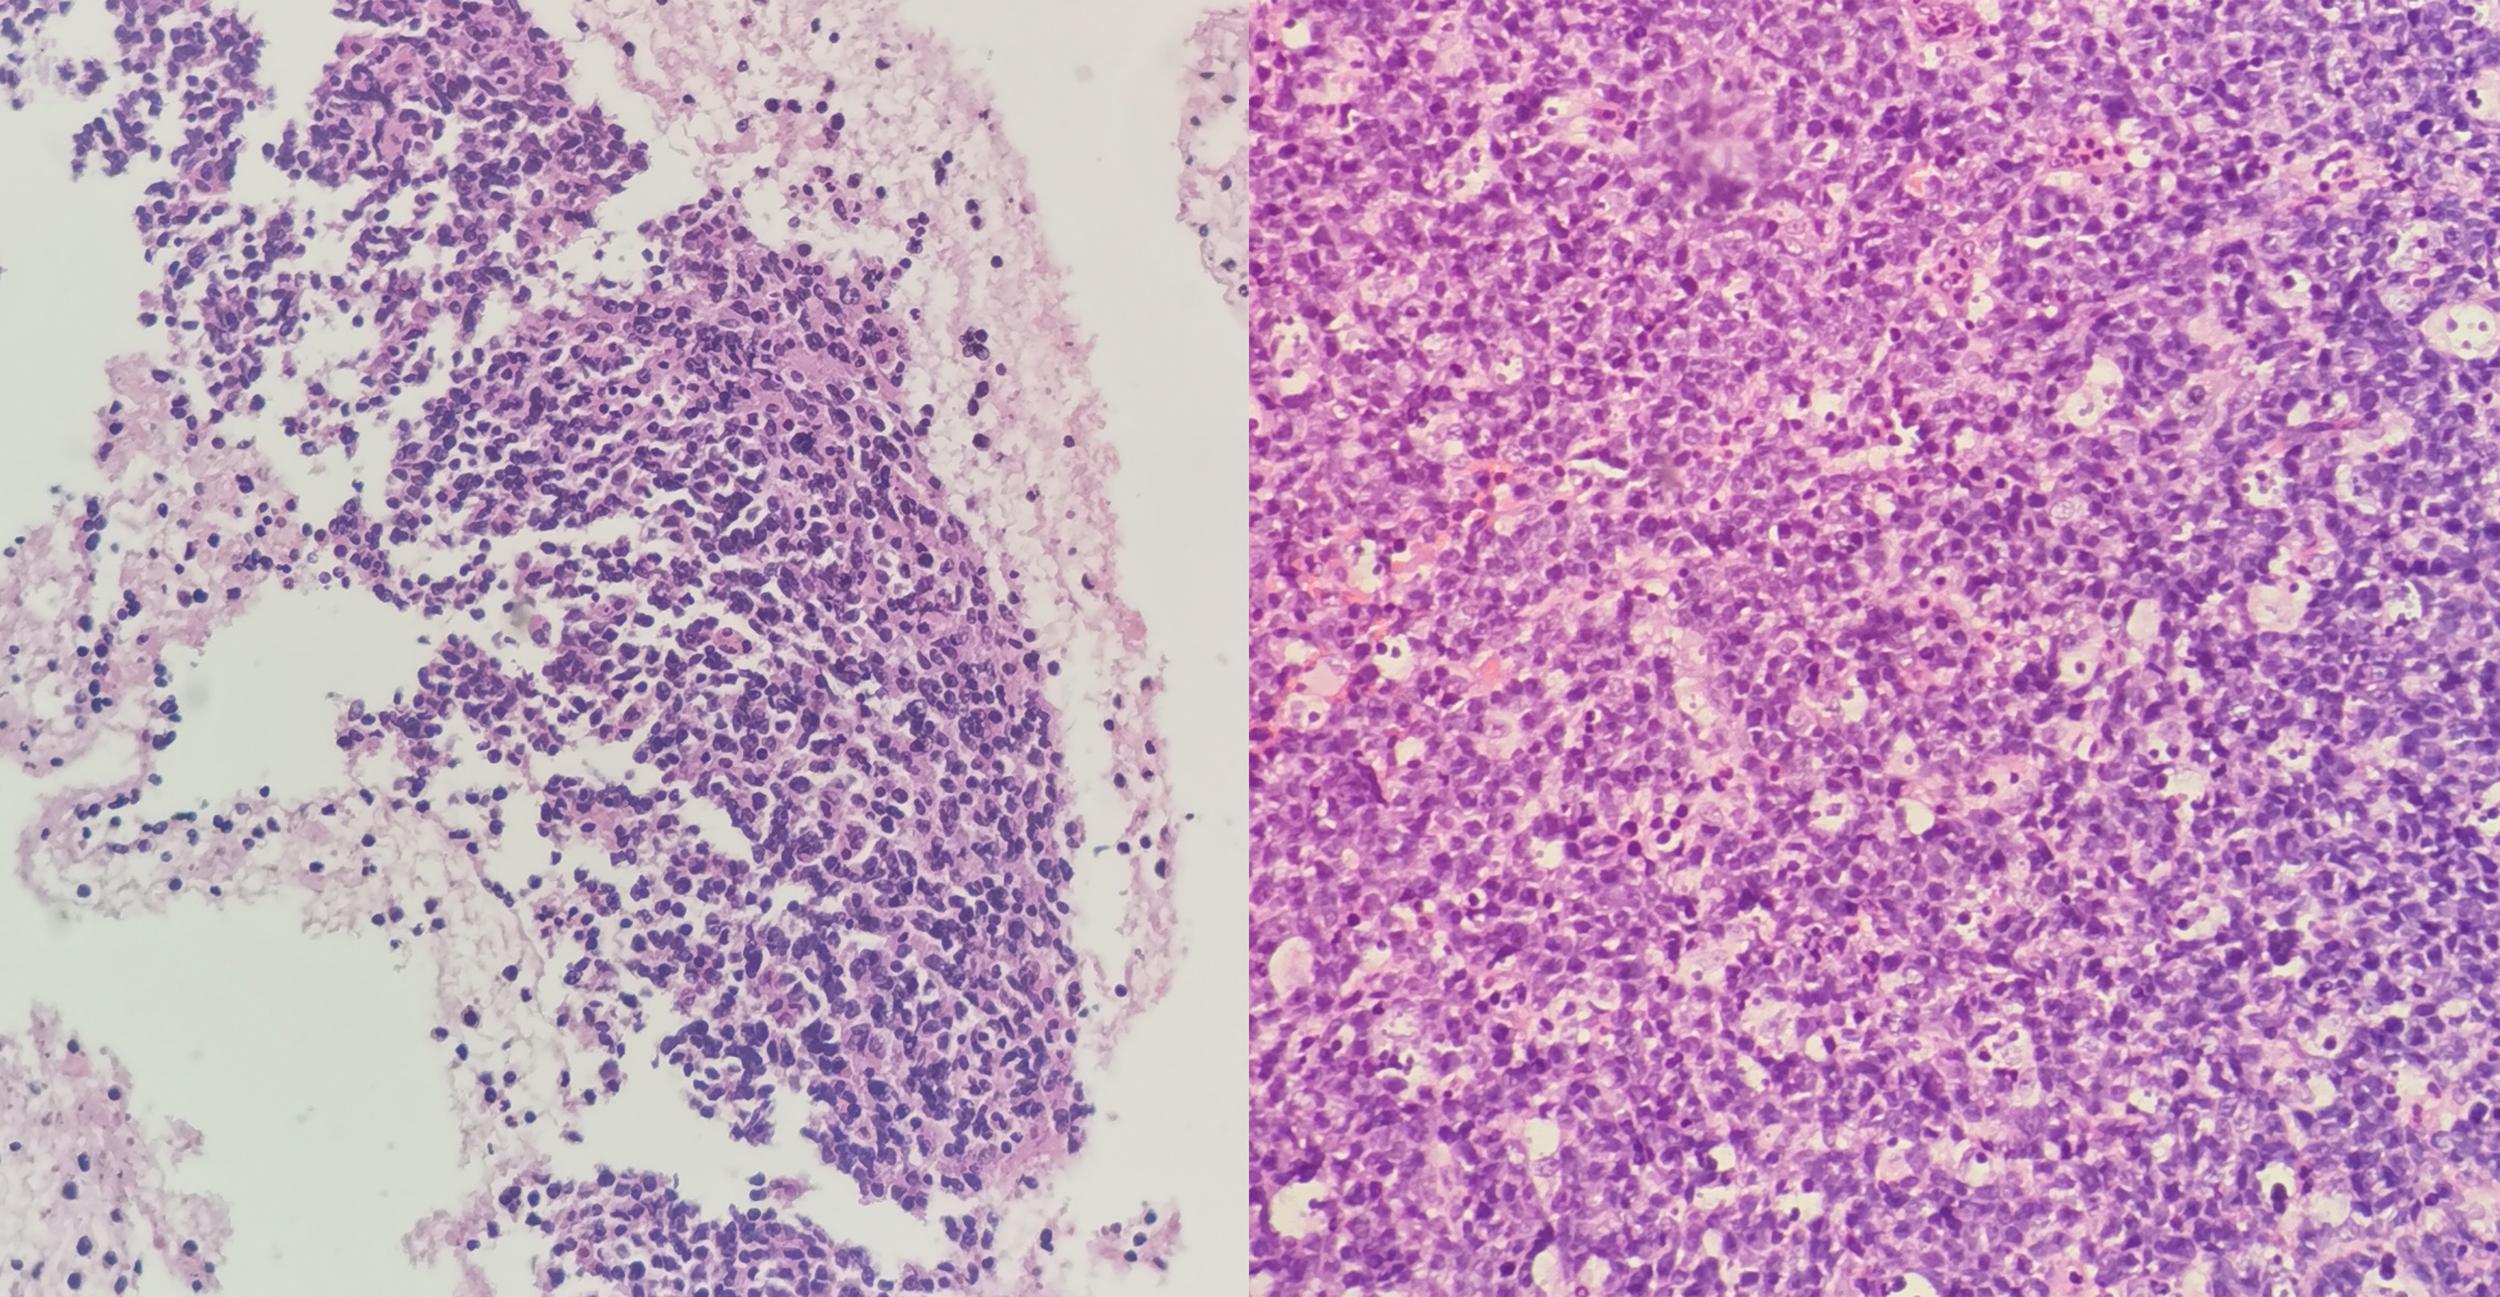

The patient underwent a series of diagnostic assessments. Initial gastroscopy revealed a significant submucosal bulge in the middle segment of the esophagus (Figure 1A). Then, a contrast-enhanced computed tomography scan of the chest showed a left main bronchus nodule measuring 15 mm, mediastinal lymph node enlargement, and fusion with necrosis (Figure 1B). Subsequently, we obtained the tissue from the mediastinal mass through EUS-FNA (Figures 1C, D) and the tissue from the left main bronchus nodule through transbronchoscope biopsy (Figures 1E, F). Both of the samples’ pathological results revealed a large number of tumor cells proliferating diffusely. The tumor cells were medium to large, and the cytoplasm was rich and transparent. The nucleus was round or oval, and the nuclear chromatin consisted of coarse particles or vacuoles. Tumor cells were often divided into nests by proliferating fibrous cords (Figure 2). Based on clinical evidence, the patient was considered to have a lymphoma. Due to the complexity of lymphoma classification, different types of lymphoma have different treatment options, and it is very important for patients to clarify the pathological type.

Figure 2

(Left) Hematoxylin and eosin (H&E) shows medium to large tumor cells with transparent cytoplasm of the mediastinal masses. (Right) H&E shows medium to large tumor cells with transparent cytoplasm of the left bronchus nodule.